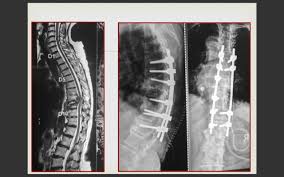

The good news is that most cases of spinal tuberculosis can be completely cured just with standard anti tuberculosis medicines. Once a diagnosis of spine tuberculosis is confirmed, your doctor will start you on anti TB treatment (ATT) for 9-12 months. This will typically comprise of 4 drugs – Isoniazid, Rifampicin, Pyrazinamide and Ethambutol. More than 90% patients improve on ATT but a few patients may need Spine Surgery in addition to ATT.